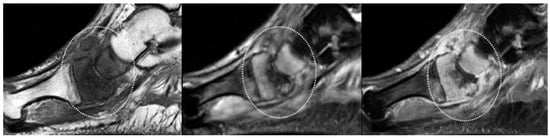

- Septic arthritis: Similar to OM and tenosynovitis, septic arthritis occurs also as a result of contiguous spread from an adjacent ulcer, abscess, or sinus tract. No single MRI feature can differentiate septic from nonseptic arthritis; increased joint fluid and synovial thickening with contrast enhancement may also be seen in non-infectious inflammatory arthropathies. However, in pedal infections, the diagnosis of septic arthritis may be more specific if an ulcer and adjacent soft-tissue infection directly abut the joint, or, a sinus tract extends into the joint. Septic arthritis may demonstrate edema with post-contrast enhancement in adjacent soft tissue and on both sides of the joint. Reactive BM oedema, secondary to septic arthritis, should be differentiated from a superimposed OM. A low signal intensity on T1-weighted images, and proximal extension of subchondral edema beyond the subchondral bone usually indicate OM [42,48].